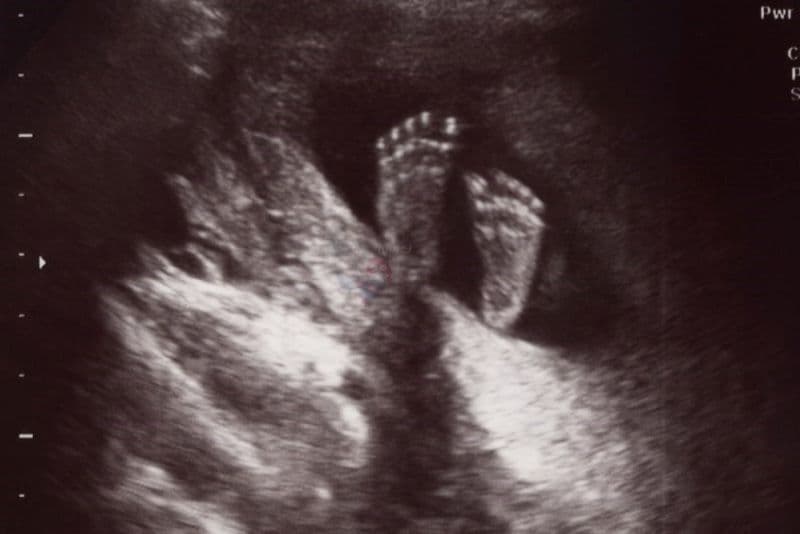

Chiều dài bàn chân của thai nhi được xác định là kích thước dài nhất tính theo trục dọc của bàn chân. Khi siêu âm, bác sĩ sẽ tiến hành đo khoảng cách từ phần gót chân đến đầu của ngón chân dài nhất (thường là ngón thứ nhất hoặc ngón thứ hai).

2. Bảng chiều dài bàn chân thai nhi theo tuần

Sự hình thành và phát triển của em bé diễn ra liên tục, do đó kích thước bàn chân cũng sẽ thay đổi tương ứng theo từng giai đoạn. Dưới đây là bảng tổng hợp chiều dài bàn chân thai nhi theo tuần để mẹ bầu có thể dễ dàng theo dõi sự thay đổi kỳ diệu này: